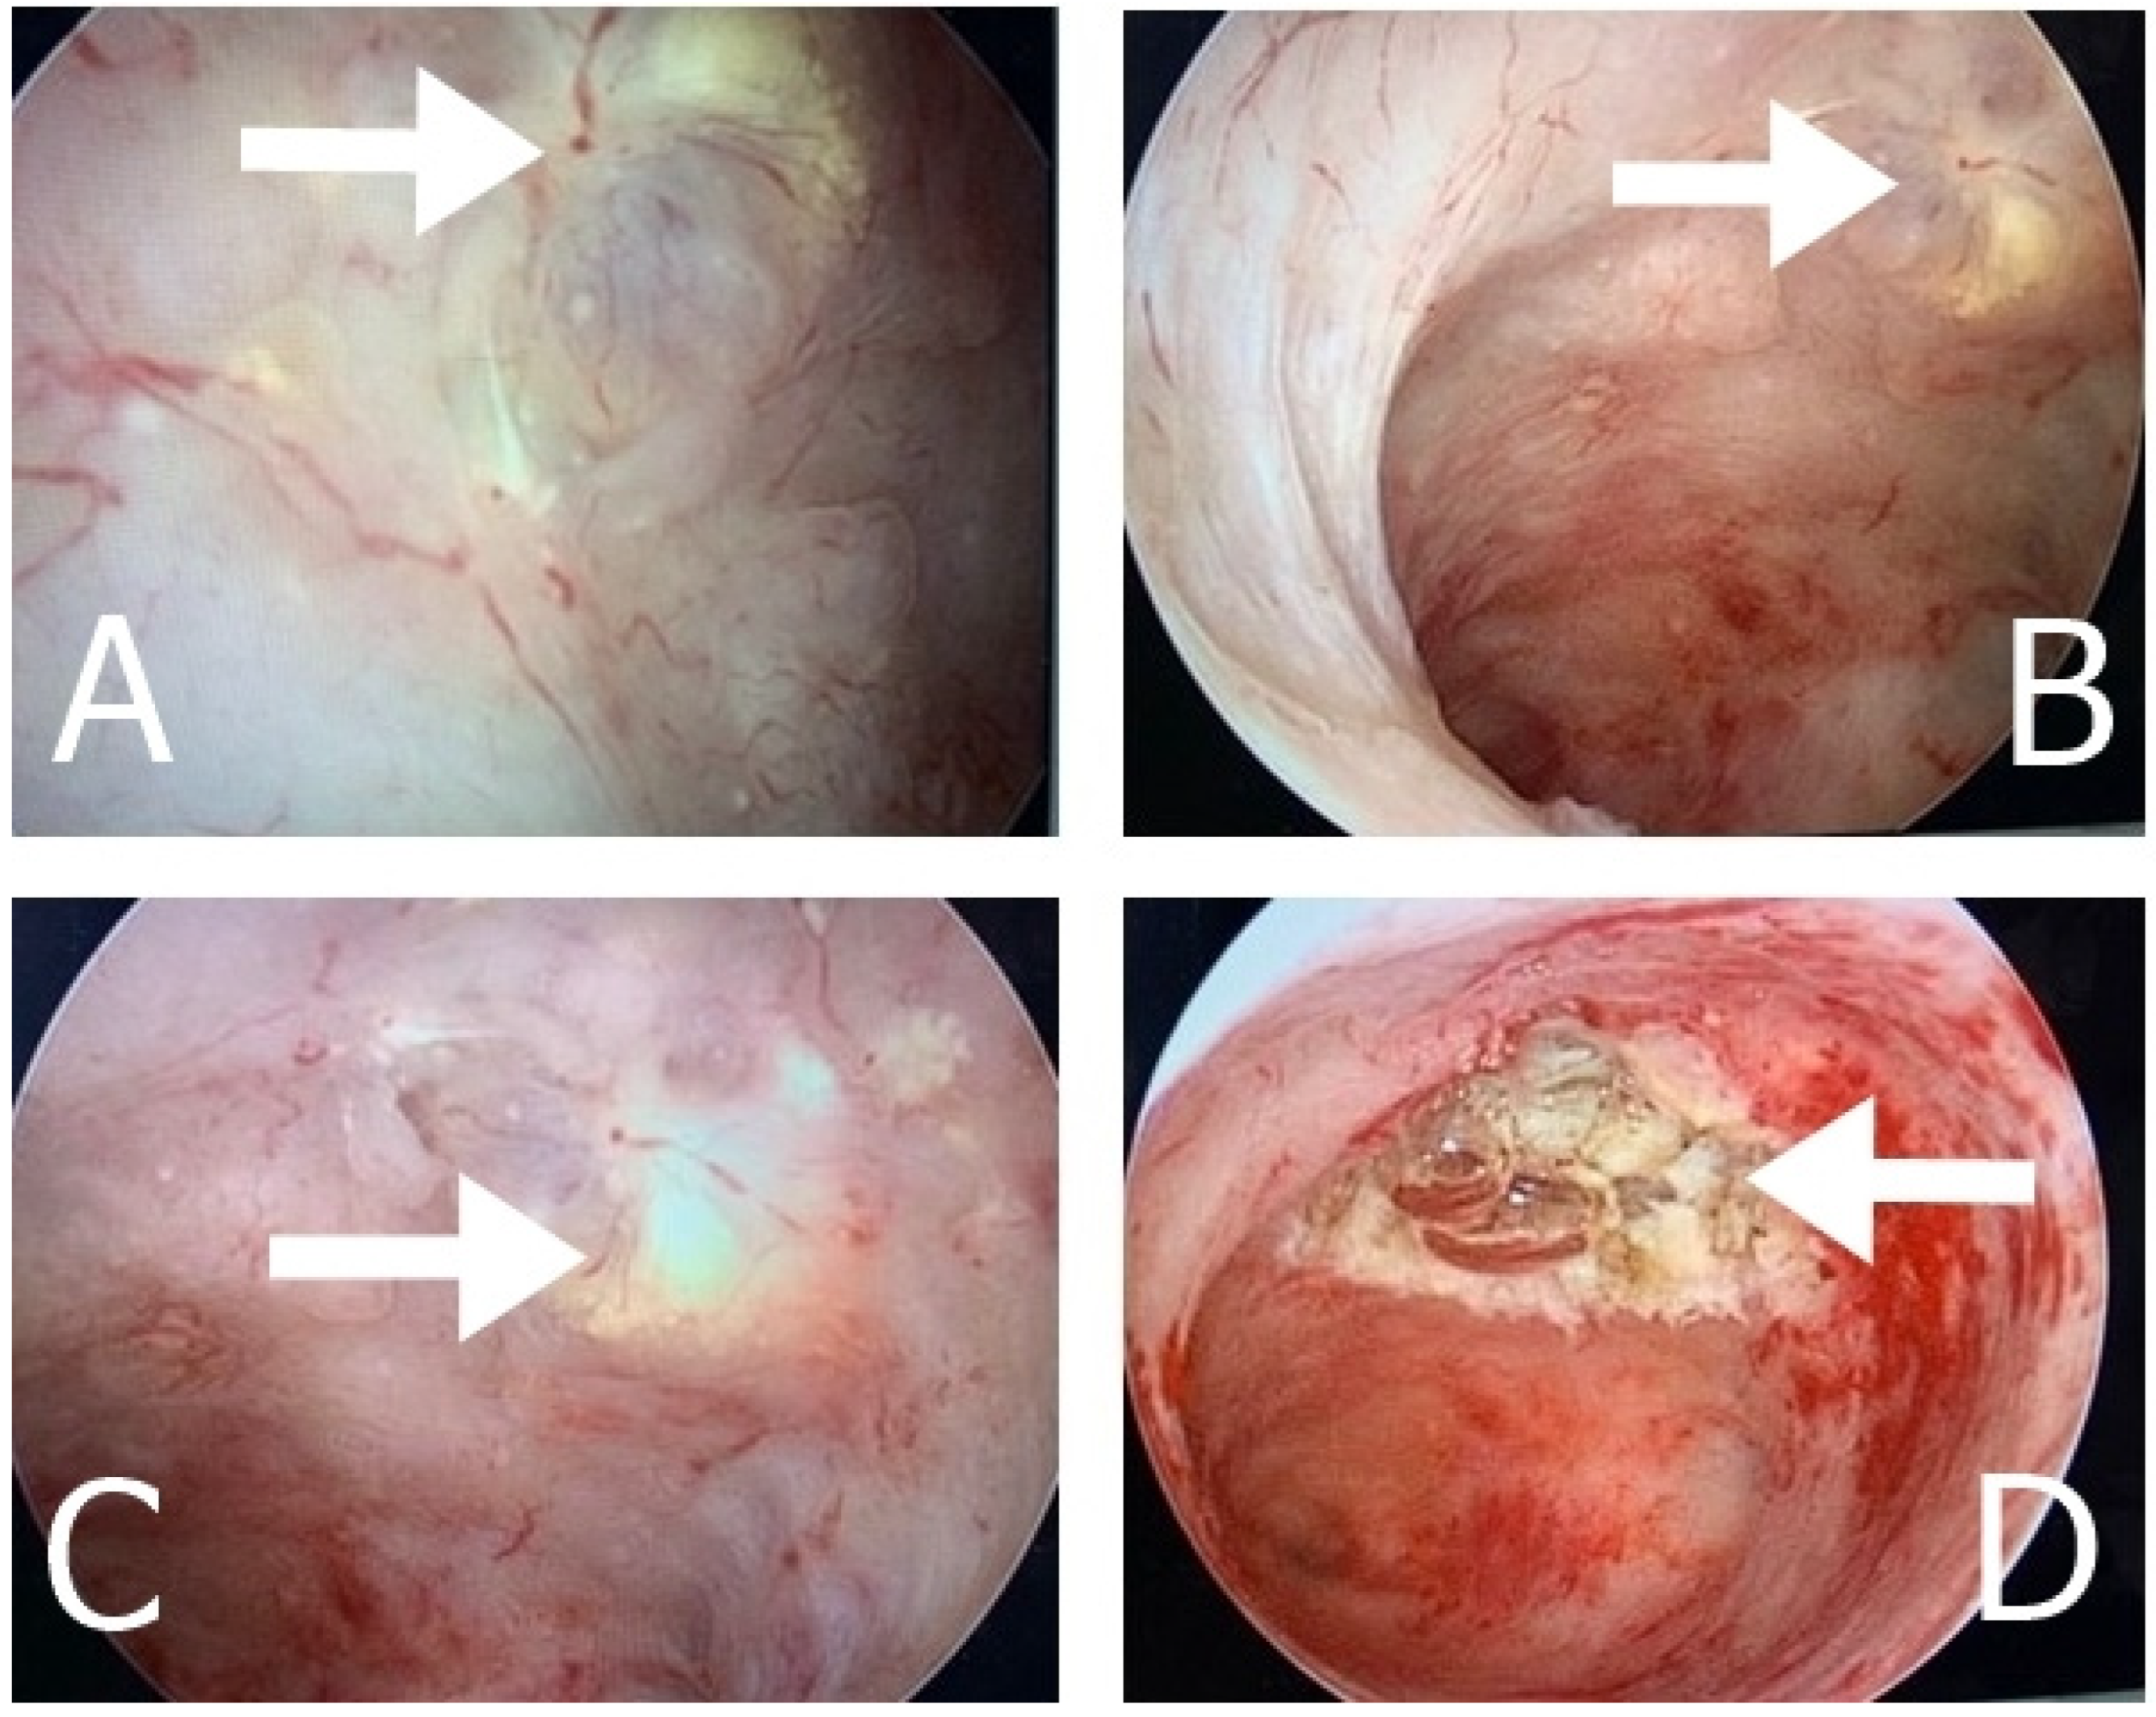

2.1. Case 1

2.2. Case 2